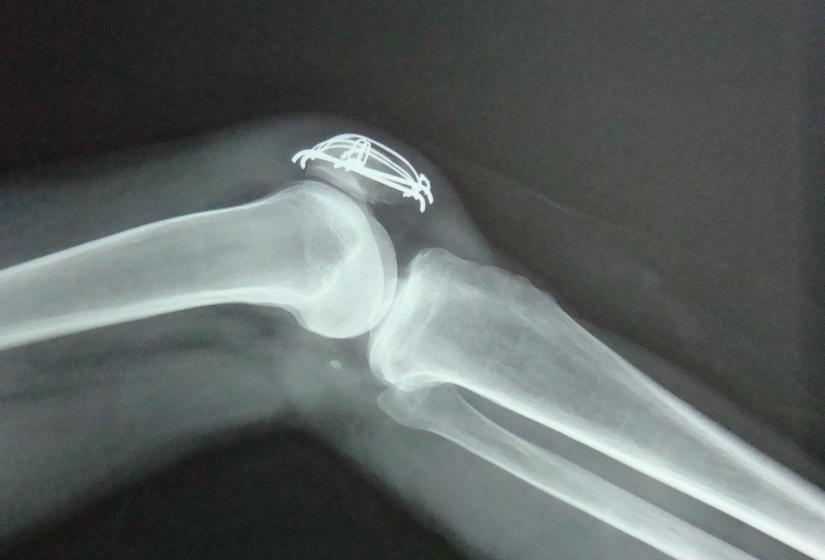

滑液是由滑膜分泌的一种能润滑关节、减少摩擦、营养软骨的透明粘质液体。正常情况下,膝关节的滑液大概在10~20毫升。但如果关节受损、滑膜受到刺激,滑液的吸收和分泌就会受到影响,在关节腔里形成了积液。

关节里水多了,会增大腔内压力,刺激周围神经,导致疼痛加剧,还伴有反射性肌痉挛。